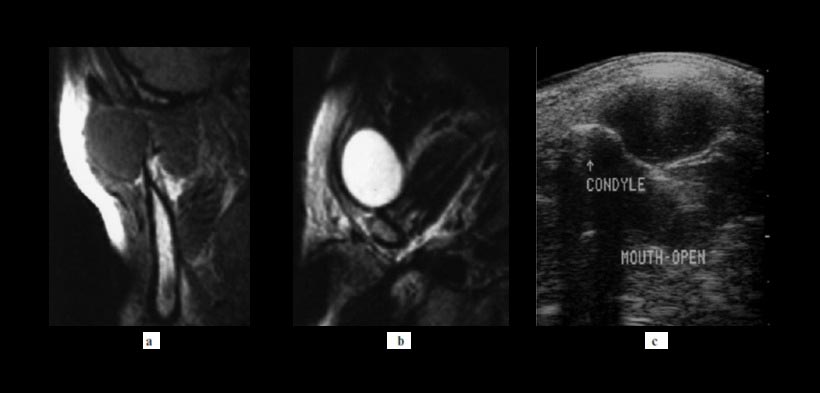

Figura 3. Paciente femenino de 37 años de edad, se dio cuenta de la hinchazón al abrir la boca en su región temporomandibular izquierda. No se observó limitación de la apertura bucal (42 mm de máxima apertura interincisal). Un examen histopatológico indicó que el tumor era un (a) Imágenes de resonancia magnética (RM) T1 demostraron una lesión bien circunscrita ovalada de masas que fue homogénea y isointensas al músculo delante de la articulación temporomandibular derecha. (b) T2 imágenes ponderadas mostraron la lesión es homogénea e hiperintensa. (c) las imágenes de ecografía mostraron una lesión bien definida, ovoide, hipoecoica y principalmente homogénea, pero con un ligero eco interno, lesión de masa con realce acústico posterior.